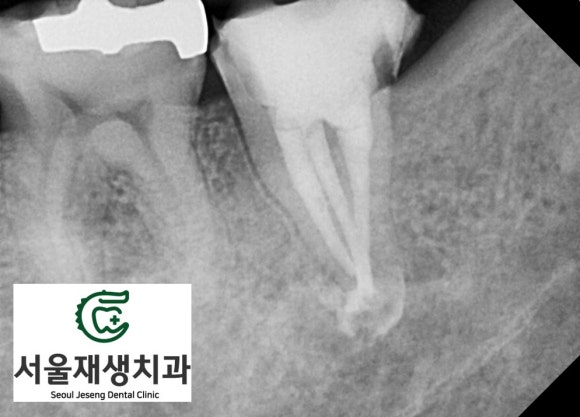

사진 상 오른쪽 아래에 보이는 치아가 심상치 않습니다.

신경치료를 하다가 중단된 상태.

뿌리 끝엔 둥근 염증주머니까지.

무슨 일이 있었던 걸까요?